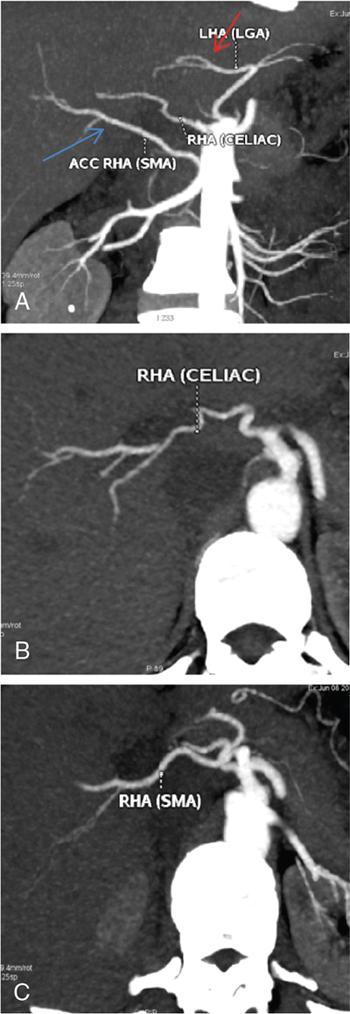

Ritu K. Kashikar, Shrinivas B. Desai Imaging is the mainstay of noninvasive diagnosis of the spectrum of abdominal pathologies or proving absence off thereof. Knowledge of normal anatomy and important normal variants is thus essential for the radiologist in order to avoid misinterpretation or erroneous diagnosis. This chapter highlights the normal anatomy of the hepatobiliary systems including the blood vessel and draining ducts and discusses relevant anatomical variants which may have important clinic implications. The liver is the largest abdominal organ, occupying the right upper abdominal quadrant and is in close approximation with the diaphragm, stomach and the gallbladder. It is largely covered by the costal cartilages. The liver is encapsulated by Glisson’s capsule which is a dense layer of connective tissue. It is covered by peritoneum, except in the regions of gallbladder fossa, fossa for inferior vena cava (IVC), and the bare area. The bare area is the posterocranial aspect of the liver, adjacent to the dorsal body wall, which is not covered by peritoneum. The liver has two surfaces, the convex diaphragmatic surface and a concave visceral surface. The slit in the hepatic hilum is called the porta hepatis and is penetrated by the right and left hepatic ducts (LHDs), hepatic artery and portal vein (PV). The distal portion of the lesser omentum is called the hepatoduodenal ligament and contains the common bile duct (CBD), hepatic artery, PV, nerves of liver and lymphatics. The liver has dual blood supply with hepatic artery providing 25% of hepatic blood and rest by portal vein (Fig. 9.2.1). Five ligaments connect the liver to the undersurface of the diaphragm. These include the falciform, the coronary and two lateral ligaments, all of which are peritoneal folds. The fifth ligament is a fibrous cord-like structure and represents the obliterated umbilical vein. The peritoneum invaginates into the liver parenchyma leading to formation of fissures. There are four normal fissures: fissures for the ligamentum teres, ligamentum venosum and gallbladder and the transverse fissure (Fig. 9.2.2). The liver is organized into microscopic functional units called lobules or acini. A central terminal hepatic venule surrounded by four to six terminal portal triads form a polygonal unit called the hepatic lobule. The terminal portal triad branches line the periphery of the unit. Between the terminal portal triads and the central hepatic venule the hepatocytes are arranged in one cell thick plates, surrounded by sinusoids. The blood flows from the terminal portal triad through sinusoids into terminal hepatic venule. Bile formed within the hepatocytes empties into terminal canaliculi which coalesce into the bile ducts (Fig. 9.2.3). This structure of the functional hepatic unit forms the basis of various functions of the liver. The normal relations of the liver are: The liver can be divided into right, left and caudate lobes. The right and left lobes are separated by the interlobular fissure and is oriented along a line passing through the gallbladder fossa inferiorly and the middle hepatic vein (MHV) superiorly (Fig. 9.2.4). This plane runs from the left of the IVC to the left of the gallbladder fossa and is a called the Cantlie’s line. Use of standardized, segmental anatomy is imperative because it facilitates communication and treatment planning. The segmental anatomy of liver is primarily based on vascular anatomy. The right lobe is divided into anterior and posterior sectors by of the right hepatic vein (RHV). The left lobe is divided into medial and lateraI sectors by an oblique plane connecting the left hepatic vein (LHV) and the falciform ligament. The liver is divided into upper and lower segments at the level of main portal vein (MPV) bifurcation (Fig. 9.2.5). Various systems are used in classification of liver anatomy. These are discussed in Table 9.2.1. The Couinaud’s system is the most commonly used and divides eight sections/segments which are discussed in details below (Table 9.2.2). 1. Segment 1 – Caudate lobe Bounded anteriorly and medially by the fissure for ligamentum venosum (Fig. 9.2.6). 2. Segment 2: Superior segment of the left lateral sector/section Bounded medially by falciform ligament and inferiorly by plane of MPV, also known as the posterior lateral sector (Bismuth, FCAT) (Fig. 9.2.7). 3. Segment 3: Inferior segment of left lateral sector/section Bounded medially by the falciform ligament and superiorly by the plane of the MPV bifurcation, also referred to as lateral anterior sector (Bismuth, FCAT) (Fig. 9.2.8). 4. Segment 4: Left medial sector/section Bounded laterally by falciform ligament and medially by Cantlie’s line (Fig. 9.2.9). 5. Segment 5: Inferior segment of the right anterior sector/section Bounded anteriorly by the gallbladder fossa and posteriorly by the plane of the RHV, superiorly bounded by the plane of MPV bifurcation (Fig. 9.2.10). 6. Segment 6: Inferior segment of the right posterior sector/section Bounded anteriorly by plane of the RHP and superiorly by the plane of the MPV bifurcation (Fig. 9.2.11). 7. Segment 7: Superior segment of the right posterior sector/section Bounded anteriorly by the plane of the RHV and inferiorly by the plane of the MPV bifurcation (Fig. 9.2.12). 8. Segment 8: Superior segment of the right anterior sector/section Bounded anteriorly by the plane of the gallbladder fossa and MHV, posteriorly bounded by the plane of the RHV and inferiorly by the plane of the MPV bifurcation (Fig. 9.2.13). Owing to its broad area of contact with the anterior abdominal wall, the liver is an ideal organ for evaluation with sonography. Ultrasound is commonly used for evaluation of size of the liver. On longitudinal scans obtained through the midhepatic line, if the liver measures 13 cm or less, it is normal in 93% of individuals (Fig. 9.2.14). The size of liver in various planes is discussed in chapter on normograms. When the area of contact between the liver and the anterior border of the right kidney, exceeds below two thirds of the kidney, the liver is considered as enlarged. The normal liver is homogeneous with fine echoes and appears evenly bright. The hepatic veins, PV and fissures interrupt the homogeneity of the liver parenchyma (Fig. 9.2.15). The parenchymal echogenicity may vary depending on the equipment, transducer and gain settings and should be judged by comparison with internal references like right renal cortex, body of the pancreas and PV walls. When compared with the adjacent normal right renal cortex the liver normally appears hyperechoic or isoechoic. The pancreas in a young individual is hypoechoic compared to the liver, and isoechoic in middle aged adults. As age progresses and fatty infiltration of the pancreas occurs, the pancreas appears hyperechoic to the liver. The liver is hypoechoic to the spleen. The normal liver reveals a density of 55–65 HU on nonenhanced scan and should appear homogenous with the exception of hypodensity in the regions of vessels and fissures. The liver parenchymal enhancement is minimal the arterial phase, with increase in density by only approximately 10 HU. This phase is usually to access vascular anatomy and to detect neovascular enhancing lesion like HCC, metastasis. Considering the fact that 75% of heptic venous supply is from the PV, the normal hepatic parenchyma shows maximum enhancement in the portal venous phase. During the venous/delayed phase the hepatic attenuation starts falling (Fig. 9.2.16). The hepatic fissures appear as linear fat containing structures. All the four fissures are well identifies on CT (Figs. 9.2.17–9.2.20). Normal liver should demonstrate uniform T1 signal similar or isointense to the paraspinal muscles and slightly hyper intense to the spleen. No signal drop should be seen on in or opposite phase. On T2W1 images liver appears slightly hyperintense to paraspinal muscles, isointense to pancreas and hypointense to spleen (Fig. 9.2.21). Following administration of extracellular contrast agents the normal liver parenchyma enhances on PV phase similar to that seen on CT. The arterial phase is preserved to determining vascular anatomy, variants and tumoural enhancement. Gadoxetic acid (Eovist) and gadobenate dimeglumine (MultiHance) are hepatobiliary agents showing excretion by the liver. In the case of gadoxetic acid, hepatic excretion is ~50%, which allows imaging in the hepatobiliary phase at ~20 minutes following injection. Gadobenate has only 3%–5% biliary excretion with hepatobiliary phase at approximately 40 minutes (Fig. 9.2.22). This property makes these agents useful in detection of nonhepatocyte containing lesions which appear hypointense to background liver on hepatobiliary phase. Hepatic anatomic variants are relatively common and represent normal interindividual variation of liver morphology. Normal Anatomic Variants Anatomic anomalies Accessory and pseudofissures may be seen in the liver. True accessory fissures result from infolding of the peritoneum usually along the undersurface of the liver and are rare. The inferior accessory fissure is the commonest accessory fissure and divides the posterior segment of the right hepatic lobe into lateral and medial portions. Diaphragmatic slips may cause indentation over the liver surface and are not commonly seen on imaging (Fig. 9.2.23). Leftward extension of the lateral segment of the left hepatic lobe appearing as a crescentic density that wraps around the spleen is referred to as sliver of liver. The left lobe of the liver may exhibit various forms: leaf like; spatular; truncated pyramid/wedge shaped; and a bifid appearance (Fig. 9.2.24). Elongated left lobe may be mimic splenomegaly, perisplenic hypoechoic collections or less commonly tumours. Imaging clues to diagnosis are establishing contiguity with liver and visualization of parenchymal vessels coursing through. The portion of the liver that extends medially from the right lobe between the IVC and fissure for ligamentum venosum is called the caudate lobe. The caudate lobe is divided inferiorly into a lateral caudate process and a medial papillary process. The medial papillary process projects medially towards the pancreatic head and has applied importance (Fig. 9.2.25). Riedel’s lobe is a tongue-like projection from the anterior aspect of the right lobe and the most common accessory lobe of the liver. It is seen most frequently in asthenic women. The reported prevalence of RL, ranges from 3.3% to 14.5% and the prevalence is higher in women than in men. It can be 20 cm or more in length and may extend up to the iliac fossa. It is usually asymptomatic and is discovered incidentally (Fig. 9.2.26). Accessory liver lobes are defined as a supernumerary lobe of normal hepatic parenchyma in continuity with the liver. This is a rare entity and usually occurs as a result of congenital ectopic hepatic tissue, although rarely may occur as a result of trauma or surgery. Various systems are proposed for classification of ALL. Another method of classification has been proposed based on biliary drainage and presence or absence of capsule. Accessory lobes can be readily diagnosed and characterized on CT or magnetic resonance imaging (MRI) done for related or unrelated conditions. CT shows the lesion as a soft–tissue density mass attached to the liver and isodense to the organ. The portal/hepatic venous branches can be seen coursing through it, in contiguity with the liver (Fig. 9.2.27). The coeliac axis trifurcates into common hepatic, splenic and left gastric arteries at the level of T12–L1. The common hepatic artery becomes the proper hepatic artery after origin of the gastro-duodenal artery. The hepatic artery proper ascends anterior to the PV and medial to the CBD and divides in to right and left hepatic artery (LHA). Occasionally the middle hepatic (segment 4) artery arises from hepatic artery proper. The hepatic artery appears as a tubular hypoechoic structure and shows antegrade flow on Doppler (Fig. 9.2.28). Normally the resistive index is low ranging between 0.55 and 0.7. The hepatic artery, its anatomy, branches, course, calibre are best evaluated on arterial phase of dynamic CT (Fig. 9.2.29). This is also the preferred modality prior to hepatobiliary surgical planning. Contrast-enhanced MRI also shows the above details but spatial resolution is lower. Road map of the arterial vascularity of the donor and recipient is a prerequisite for transplant surgery and complex hepatobiliary surgery. Detailed hepatic arterial anatomy and its variations have its significance in liver surgeries and interventional hepatic procedures, relative to the hepatic lobe involved. A classification method was described by Michel et al. in 1955, and is discussed in Table 9.2.3 (Fig. 9.2.30). I: standard anatomy ~60% (range 55%–61%) II: replaced LHA ∼7.5% (range 3%–10%) III: replaced RHA ~10% (range 8%–11 %) IV: replaced RHA and LHA ~1% V: accessory LHA from LGA ~10% (range 8%–11%) VI: accessory RHA from SMA ~5% (range 1.5%–7%) VII: accessory RHA and LHA ~1% VIII: accessory RHA and LHA and replaced LHA or RHA ~2.5% IX: CHA replaced to SMA ~3% (range 2%–4.5%) X: CHA replaced to LGA ~0.5% Other unclassified variants are: The two most common variants are the replaced right hepatic artery (RHA) arising from the SMA (Fig. 9.2.31) and replaced LHA arising from the left gastric artery (Figs. 9.2.32–9.2.34). Segment 4 artery – Middle hepatic artery (MHA) The middle hepatic artery usually arises from the LHA, it may, however, arise from the RHA (Fig. 9.2.35). The knowledge regarding origin of MHA is imperative in transplant surgery. The MHA can arise from RHA in Patients with replaced LHA. In patients with replaced RHA, the MHA arises from LHA (Fig. 9.2.36). Because of the considerable variability of hepatic arterial anatomy, assessment of this anatomy is crucial in the preoperative evaluation of potential living liver donors. Relevance of donor and recipient arterial anatomy is discussed in details in chapter on liver transplant. The relationship between the arterial variant and tumour is important to establish prior to major surgeries. Injuries to aberrant hepatic vessels and secondary ischaemic biliary strictures can be avoided. A replaced RHA has a more posterior course and long length. This variant may be advantageous in patients undergoing right lobar resection. However, there is greater propensity of involvement of replaced RHA by pancreatic head. The radiologist must be vigilant in reporting this variant (Fig. 9.2.37). Accessory RHA can, however, be sacrificed even if encased by neoplasm. An accessory LHA needs to be ligated separately in surgeries where blood supply in the porta hepatis is occluded. Replaced LHA from LGA maybe injured in case of surgeries at the level of hiatus. Hence this variant should be informed to surgeon in patients undergoing gastric surgeries. Preoperative mapping of the hepatic arterial anatomy prior to placement of intraarterial chemotherapy pumps is essential because it helps in deciding whether the candidate is suitable for the procedure and also if technical modifications are needed. The intraarterial infusion pump should be placed in the dominant hepatic artery as proximal as possible, but beyond GDA origin. Inpatients with standard anatomy, the pump is usually placed in the hepatic artery prior just after GDA origin. The location of pump can be modified in patients with variant anatomy, based on origin of GDA and dominant hepatic vessel. The PV is the main vessel in the portal venous system and drains blood from the gastrointestinal tract and spleen to the liver.